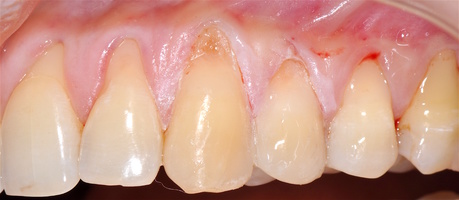

В области от 1.6 до 2.6 и от 3.6 до 4.6 все зубы имеют некариозные поражения разной степени, такие как эрозии эмали и клиновидные дефекты, вовлекающие в процесс ткани эмали и дентина. Подвижности зубов не выявлено (рис. 1а-е) [9].

При анализе и описании компьютерной конусно-лучевой томографии (рис. 2а-г) была выявлена генерализованная первичная дегисценция вестибулярной пластинки кости от 1/2 до 3/4 длины корней зубов, зубной ряд целостный, все зубы витальны, кариозных поражений нет. Тип кости 1-2 (Lechkolm и Zarb, 1983), первичная дегисценция вестибулярной костной пластинки превышает пределы возрастной атрофии.